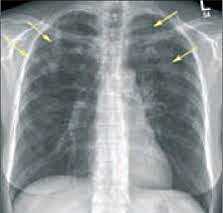

- Рентгенография легких. На снимках видны субплеврально расположенные одиночные (реже множественные, двусторонние) нечеткие затемнения средней интенсивности неправильной формы размером до 3-4 см. В окружении инфильтрата легочный рисунок усилен, тень корня легкого слегка расширена. Характерна быстрая динамика инфильтратов с миграцией по легочным полям и исчезновением не позднее 1-2 недель после обнаружения (чаще через 1-3 дня) без остаточной рубцовой деформации. При длительно поддерживающемся инфильтративном воспалении в ткани легких могут образоваться фиброзные очаги и кистозные полости.

- Рентгенография. Рентгенологическими признаками интерстициальной пневмонии могут являться симметричные полупрозрачные затемнения по типу «матового стекла», в основном в нижних отделах легких; утолщение междолькового и внутридолькового интерстиция; кистозно-фиброзные изменения, периваскулярная и перибронхиальная инфильтрация и тракционные бронхоэктазы.